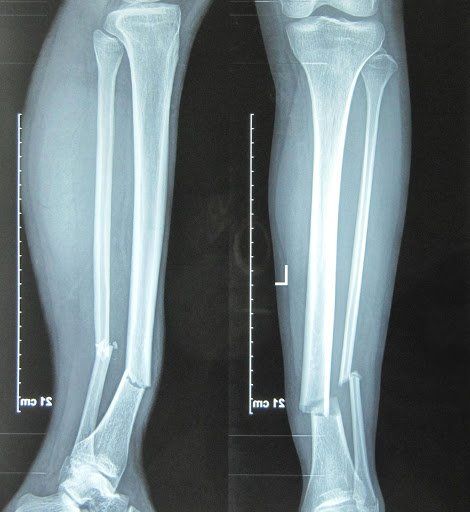

The Busby family—beloved stars of OutDaughtered—has once again found themselves in the center of public attention after a shocking revelation from Danielle Busby. Earlier this week, Danielle took to social media to share heartbreaking news: Adam Busby has suffered a serious leg injury, leaving him with a painful fracture that requires weeks, possibly months, of recovery.

Fans were stunned. Adam, known for his energetic personality, constant involvement with the quints, and his active lifestyle, is not someone people expect to see sidelined. But according to Danielle’s emotional update, the injury happened during what Adam believed would be a simple, harmless activity—something he’s done a hundred times before.